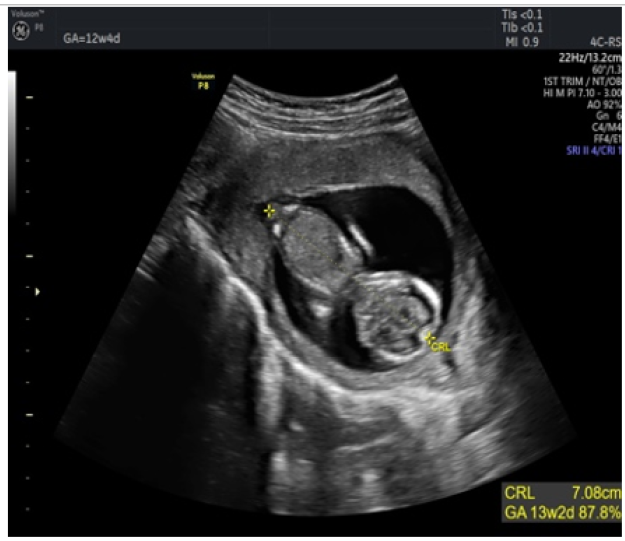

Prenatal Diagnosis of Aplasia Cutis Congenita on the Superior and Inferior Limbs with 2D Ultrasound: Case Report

Kariman Ghazal MD, Mira Hdeib MD, Imad Abou Jaoude MD and Jihad El Hassan. 12(1): 90-96.